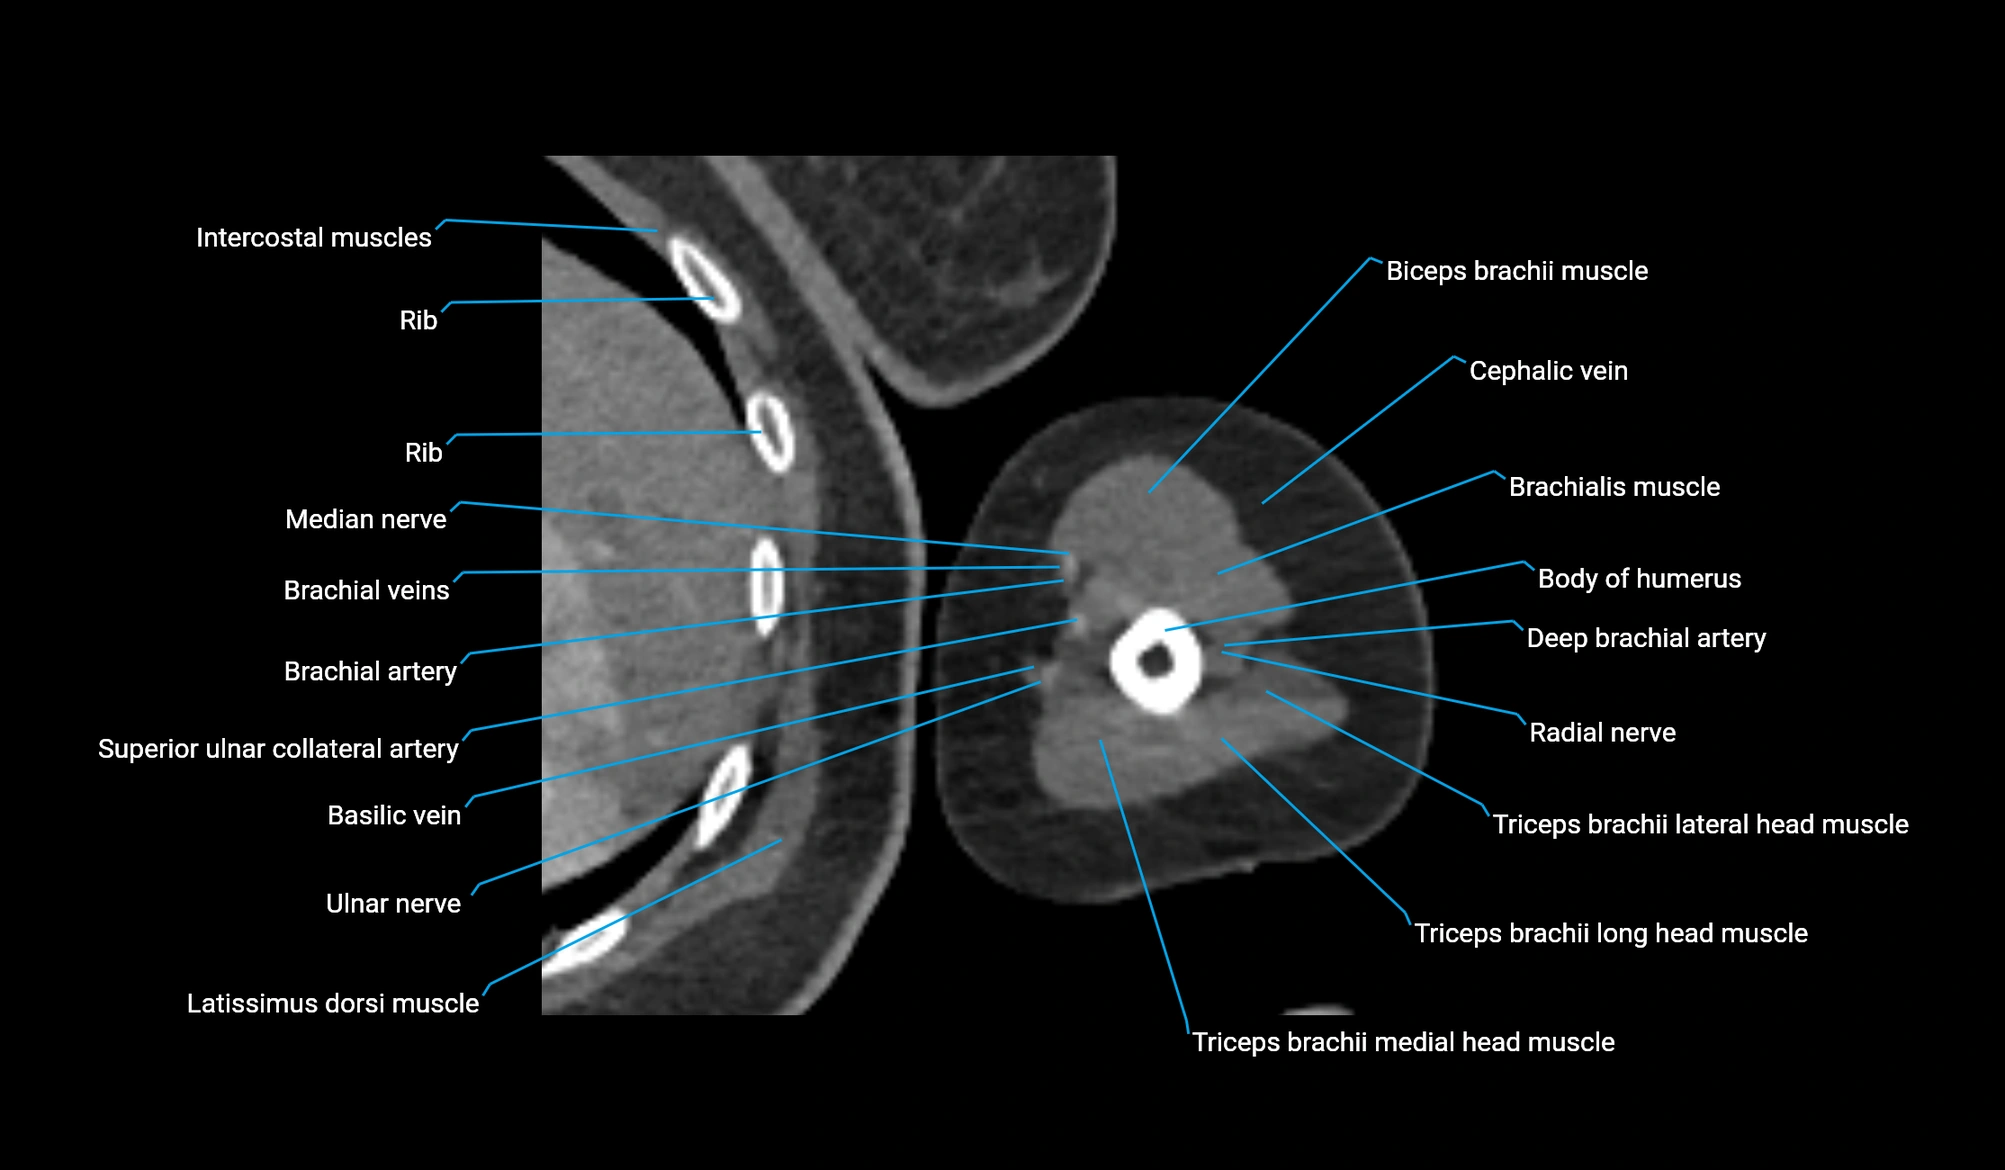

CT image